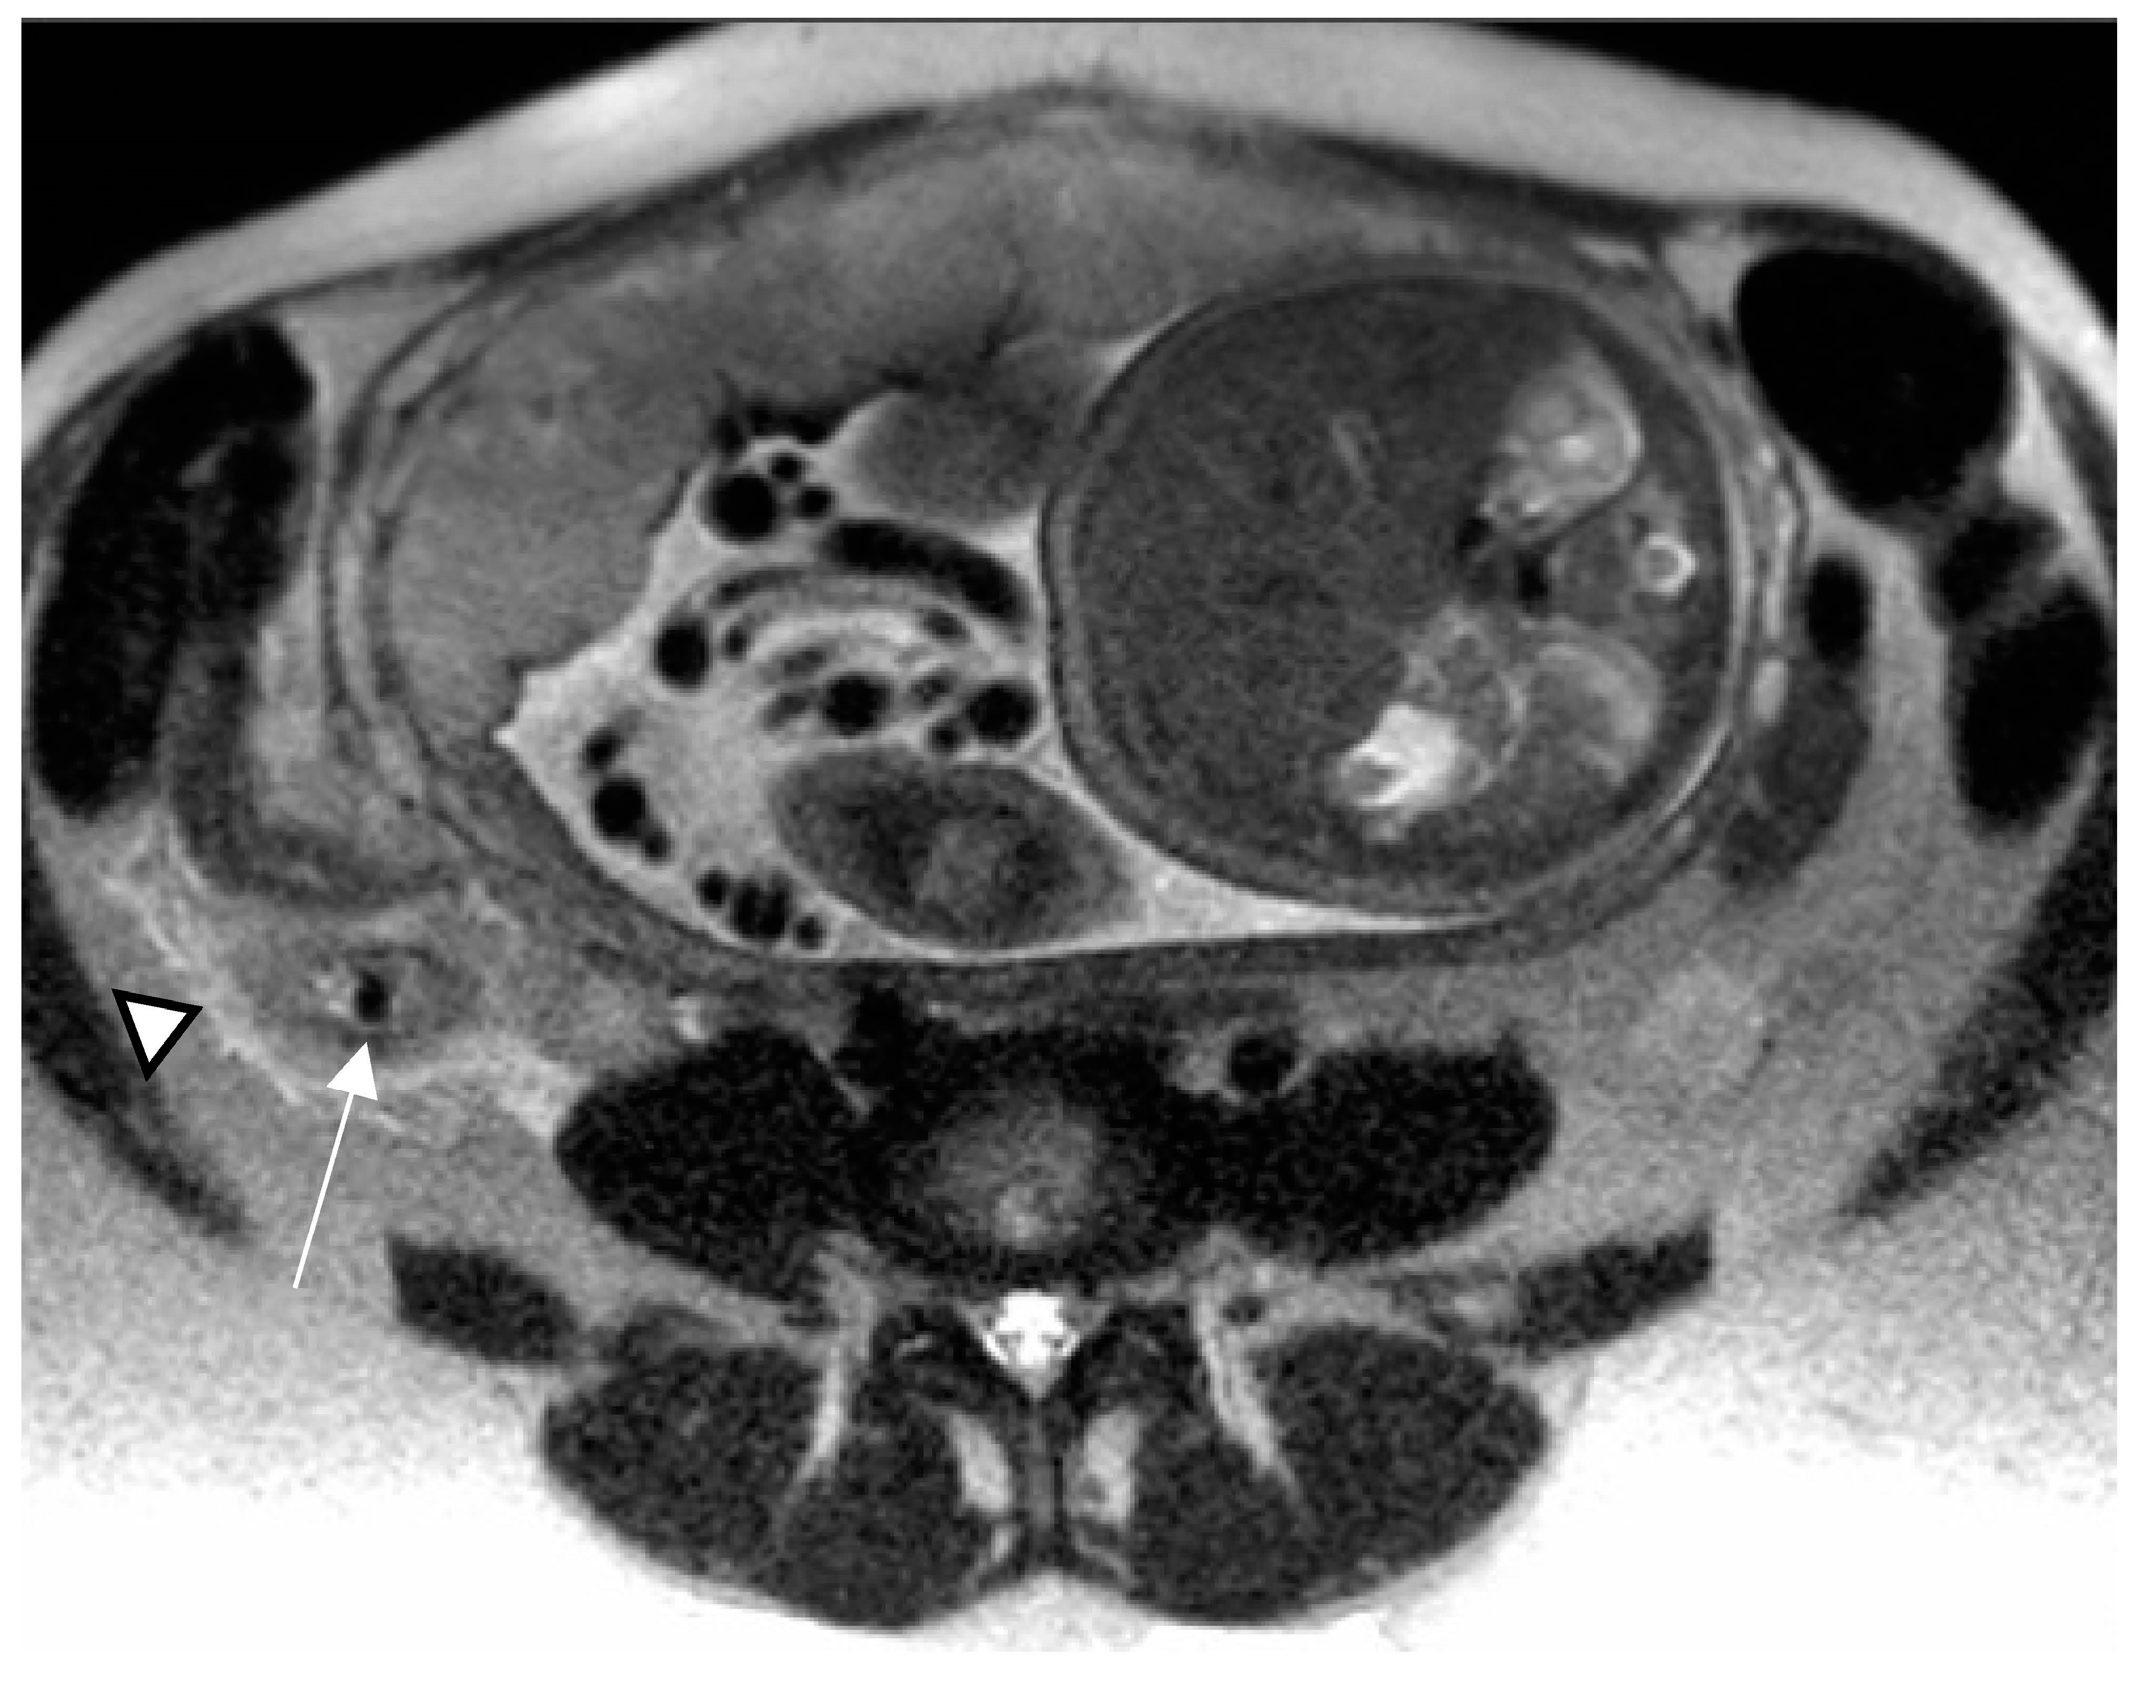

The MRI findings for AA mirror those of other modalities, including an enlarged appendix (diameter greater than 7 mm), with a thickened wall due to mural oedema (>2 mm), high signal intensity luminal contents on T2 weighted-images (T2WI) and periappendiceal fat stranding or free fluid [20]; the appendicolith may appear as a round-shaped structure hypointense on all pulse sequences (Figure 2).

Figure 2.

Acute appendicitis in a 32-year-old woman at 34 weeks gestation presenting with right-sided abdominal pain. Axial T2-weighted HASTE image demonstrates a low-signal-intensity appendicolith within a dilated and wall-thickened appendix (arrow). Periappendiceal fat stranding, caused by inflammatory changes, is also depicted (arrowhead).